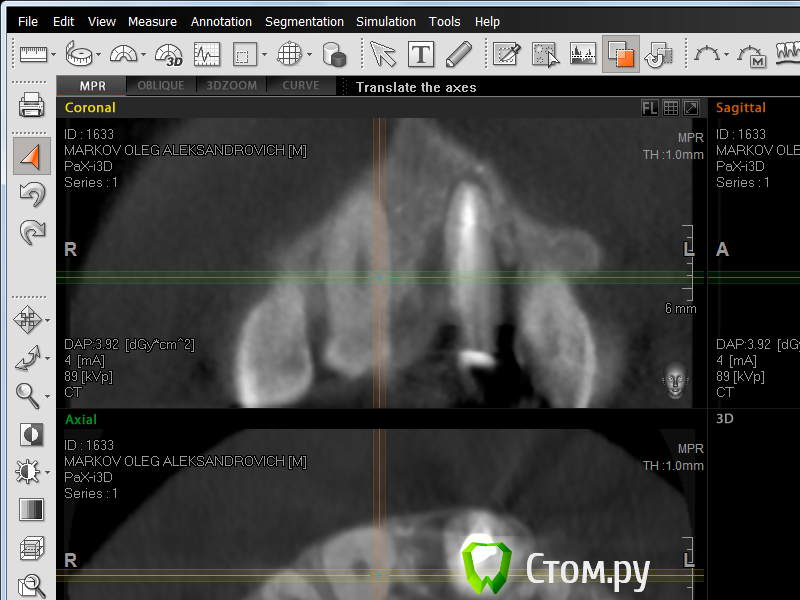

zzulon Опубликовано 31 августа, 2014 Автор Поделиться Опубликовано 31 августа, 2014 Добрый вечер!почитал тему-сделал скриншот кт,нужен совет,делать имплантацию или оставить как есть? Ссылка на комментарий

Togha Опубликовано 31 августа, 2014 Поделиться Опубликовано 31 августа, 2014 Я боюсь что вы не сможете сделать скриншот именно так, как нужно нам, а по имеющемуся предполагаю перелом корня в верхушечной трети и достаточно большую потерю костной ткани, так что зуб действительно подлежит удалению и пока что нет сомнений в грамотности вашего хирурга. Ссылка на комментарий